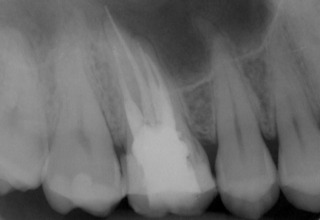

Patient N.M. wünscht eine Drittmeinung, zwischenzeitlich hatte er bereits einen zweiten Zahnarzt konsultiert. Dieser bestätigte eine insuffiziente Wurzelfüllung und vermutete eine Instrumentenfraktur im mb1 (Abb. 1).

Abb. 1: Ausgangsröntgenbild des insuffizient gefüllten Zahnes 16.

Röntgenbefund

Mittels Röntgenaufnahme lässt sich ein frakturiertes Instrument in mb1 vermuten. Des Weiteren scheint es, als sei der distale Wurzelkanal sowie der mb2 nicht abgefüllt worden, was sich zu einem späteren Zeitpunkt der Behandlung bestätigen sollte. Der Patient wurde vom vorbehandelnden Zahnarzt über die Fraktur nicht aufgeklärt.